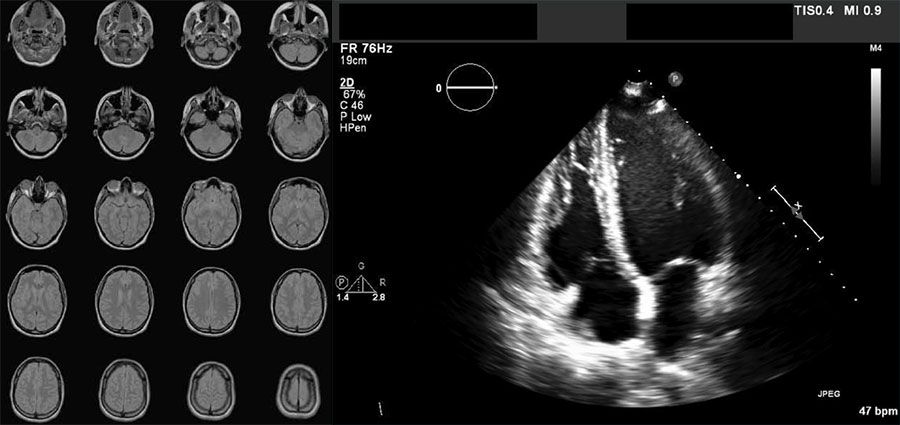

Beispiele für DICOM-formatierte Bilder: eine Serie von 20 Bildern aus MRT-Aufnahmen eines Gehirns und ein kardiales Ultraschallbild.

Im DICOM-Format gespeicherte MR-Bildserie eines Gehirns (links) und kardiale Ultraschallaufnahme (rechts).